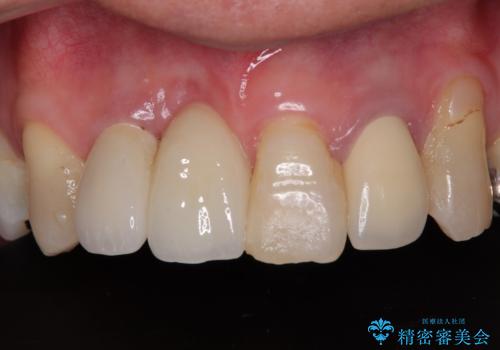

- 内側に倒れている前歯が擦れてしみるとのことで来院された患者様です。

削れていた部分は詰め物が入っていましたが、縁の部分がしみているようで、変色も目立っていたため、オールセラミッククラウンにて補綴治療を行うこととしました。